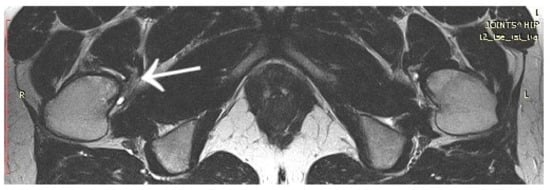

3.4. Case 4: OO Masking as a Fatigue Fracture